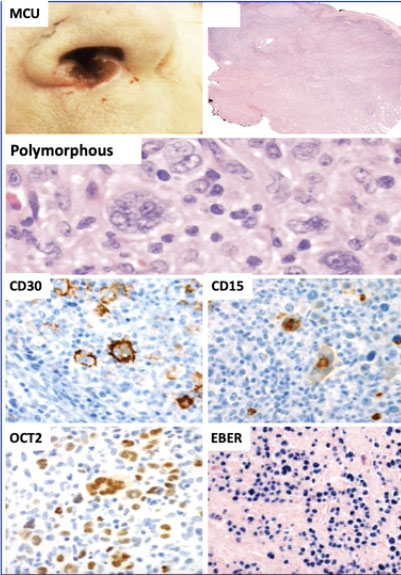

Plasmablastic lymphoma (PBL)

Primary effusion lymphoma (PEL)

HHV8-associated lymphoproliferative disorders

- HHV8-positive diffuse large B-cell lymphoma, NOS

- HHV8-positive germinotropic lymphoproliferative disorder